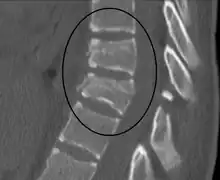

| A Chance fracture of T10 and fracture of T9 due to a seatbelt during an MVC. | |

The cause is classically a head-on motor vehicle collision in which the affected person is wearing only a lap belt.[2] Being hit in the abdomen with an object like a tree or a fall may also result in this fracture pattern.[12][10] It often involves disruption of all three columns of the vertebral body (anterior, middle, and posterior).[7][6] The most common area affected is the lower thoracic and upper lumbar spine.[6] A CT scan is recommended as part of the diagnostic work-up to detect any potential abdominal injuries.[5] The fracture is often unstable.[1]